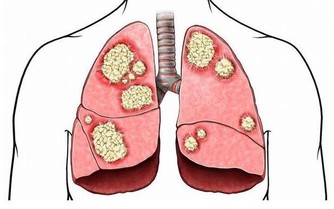

▼因此,美國國家生物技術訊息中心(National Center for Biotechnnology Information)也鼓勵人們多採用蹲姿如廁,讓人體可以在最舒適的環境下乾淨地排出體內的廢物和有害物質,從而有效降低患上第三大常見癌症-直腸癌的機率。